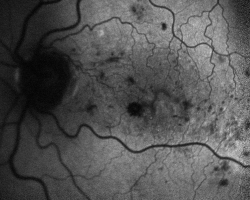

• Autofluorescence (2018)

hypoautofluorescence liée à l’œdème maculaire et aux hémorragies rétiniennes qui, par effet masque, empêchent la stimulation de l’epithélium pigmentaire rétinien